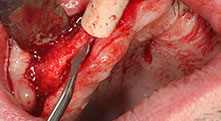

Bratu: Wir nutzen die Instrumente routinemäßig für die Entnahme von Knochenblöcken und das Spalten von Kieferkämmen. Weiterhin osteotomieren wir mit den Piezomed B6/B7 retinierte Zähne und entfernen nicht erhaltungsfähige Implantate. Alles Indikationen, bei denen es auf tiefe, saubere Schnitte ankommt.

Bratu: Wir bevorzugen Knochenentnahmen von der Linea obliqua externa des posterioren Unterkiefers, nicht aus der interforaminalen Region. Nach der Weichgewebsinzision verwenden wir die neuen Sägen, um den Umfang der Knochenentnahme zu definieren. Wir erledigen damit in fast 80 Prozent der Fälle auch die gesamte Präparation. Zusätzlich verwenden wir eventuell andere Piezo-Instrumente und zuletzt einen Meißel, um den Block zu mobilisieren. Das ist für uns eine sehr effektive Operationstechnik.